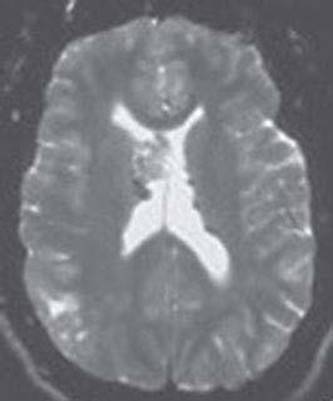

44. A 3-year-old girl with intractable seizures presents to the clinic for seizure management. On examination, she has spastic quadriparesis and requires a feeding tube because of recurrent aspirations. Images from her MRI are shown in Figure 14.4. What is the diagnosis in this patient?

FIGURE 14.4 (A) Axial T2-weighted MRI (left); (B) Coronal T1-weighted MRI. Courtesy of Dr. Ajay Gupta and Dr. Joanna Fong

45. Which of the following statements is incorrect regarding the disorder depicted in Figure 14.4?

a. It is a disorder of neuronal migration

b. It results from abnormalities in a protein involved in microtubule organization and stabilization

c. It is an X-linked disorder

d. Mutations in the DCX gene lead to this disorder in females and lissencephaly in males

e. This disorder is classically associated with muscular dystrophy